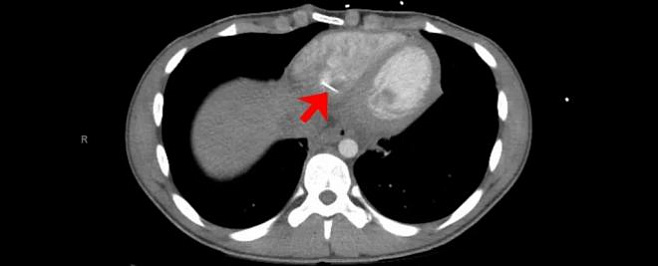

Компьютерная томография груди показала, что в его сердце застрял линейный металлический инородный объект размером около 3,5 сантиметра в длину. Он выступал из правого желудочка, который перекачивает кровь в легкие.